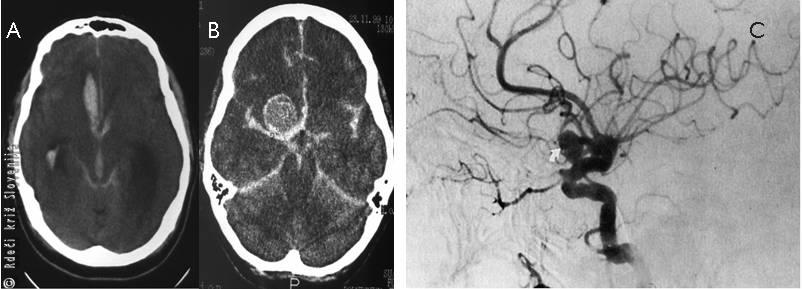

Slika 5

Ishemična možganska kap. Vzrok je lahko:

A – krvni strdek, ki se naredi v srcu in odleti v možgansko arterijo;

B – zamašitev arterije zaradi nalaganja oblog na stene arterije v možganih;

C – računalniška tomografija ishemične možganske kapi.